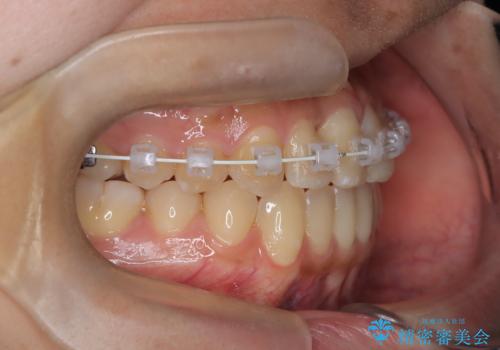

- 患者様は左上の八重歯を気にされて来院されました。八重歯による歯列の乱れだけでなく、翼状捻転(歯がねじれるように生えている状態)も見られました。目立たない矯正を希望されていたため、**インビザライン(マウスピース矯正)**を選択し、左上の小臼歯を抜歯してスペースを作りながら歯を並べる治療計画を立てました。しかし、治療の途中で翼状捻転の改善が十分に進まなかったため、患者様の希望も踏まえ、上顎のみワイヤー矯正に変更することとなりました。

治療開始時はインビザラインを使用し、全体の歯並びを整えながら抜歯スペースを活用して歯を後方へ移動させました。しかし、左上の八重歯のねじれが強く、マウスピースのみでは十分にコントロールできないことが判明。そこで、より細かく歯を動かすために上顎のみワイヤー矯正へ切り替えました。ワイヤー矯正によって翼状捻転も改善し、最終的にバランスの取れた歯並びと噛み合わせを実現。患者様からは「長い治療だったけれど、しっかり整って満足」と嬉しいお言葉をいただきました。